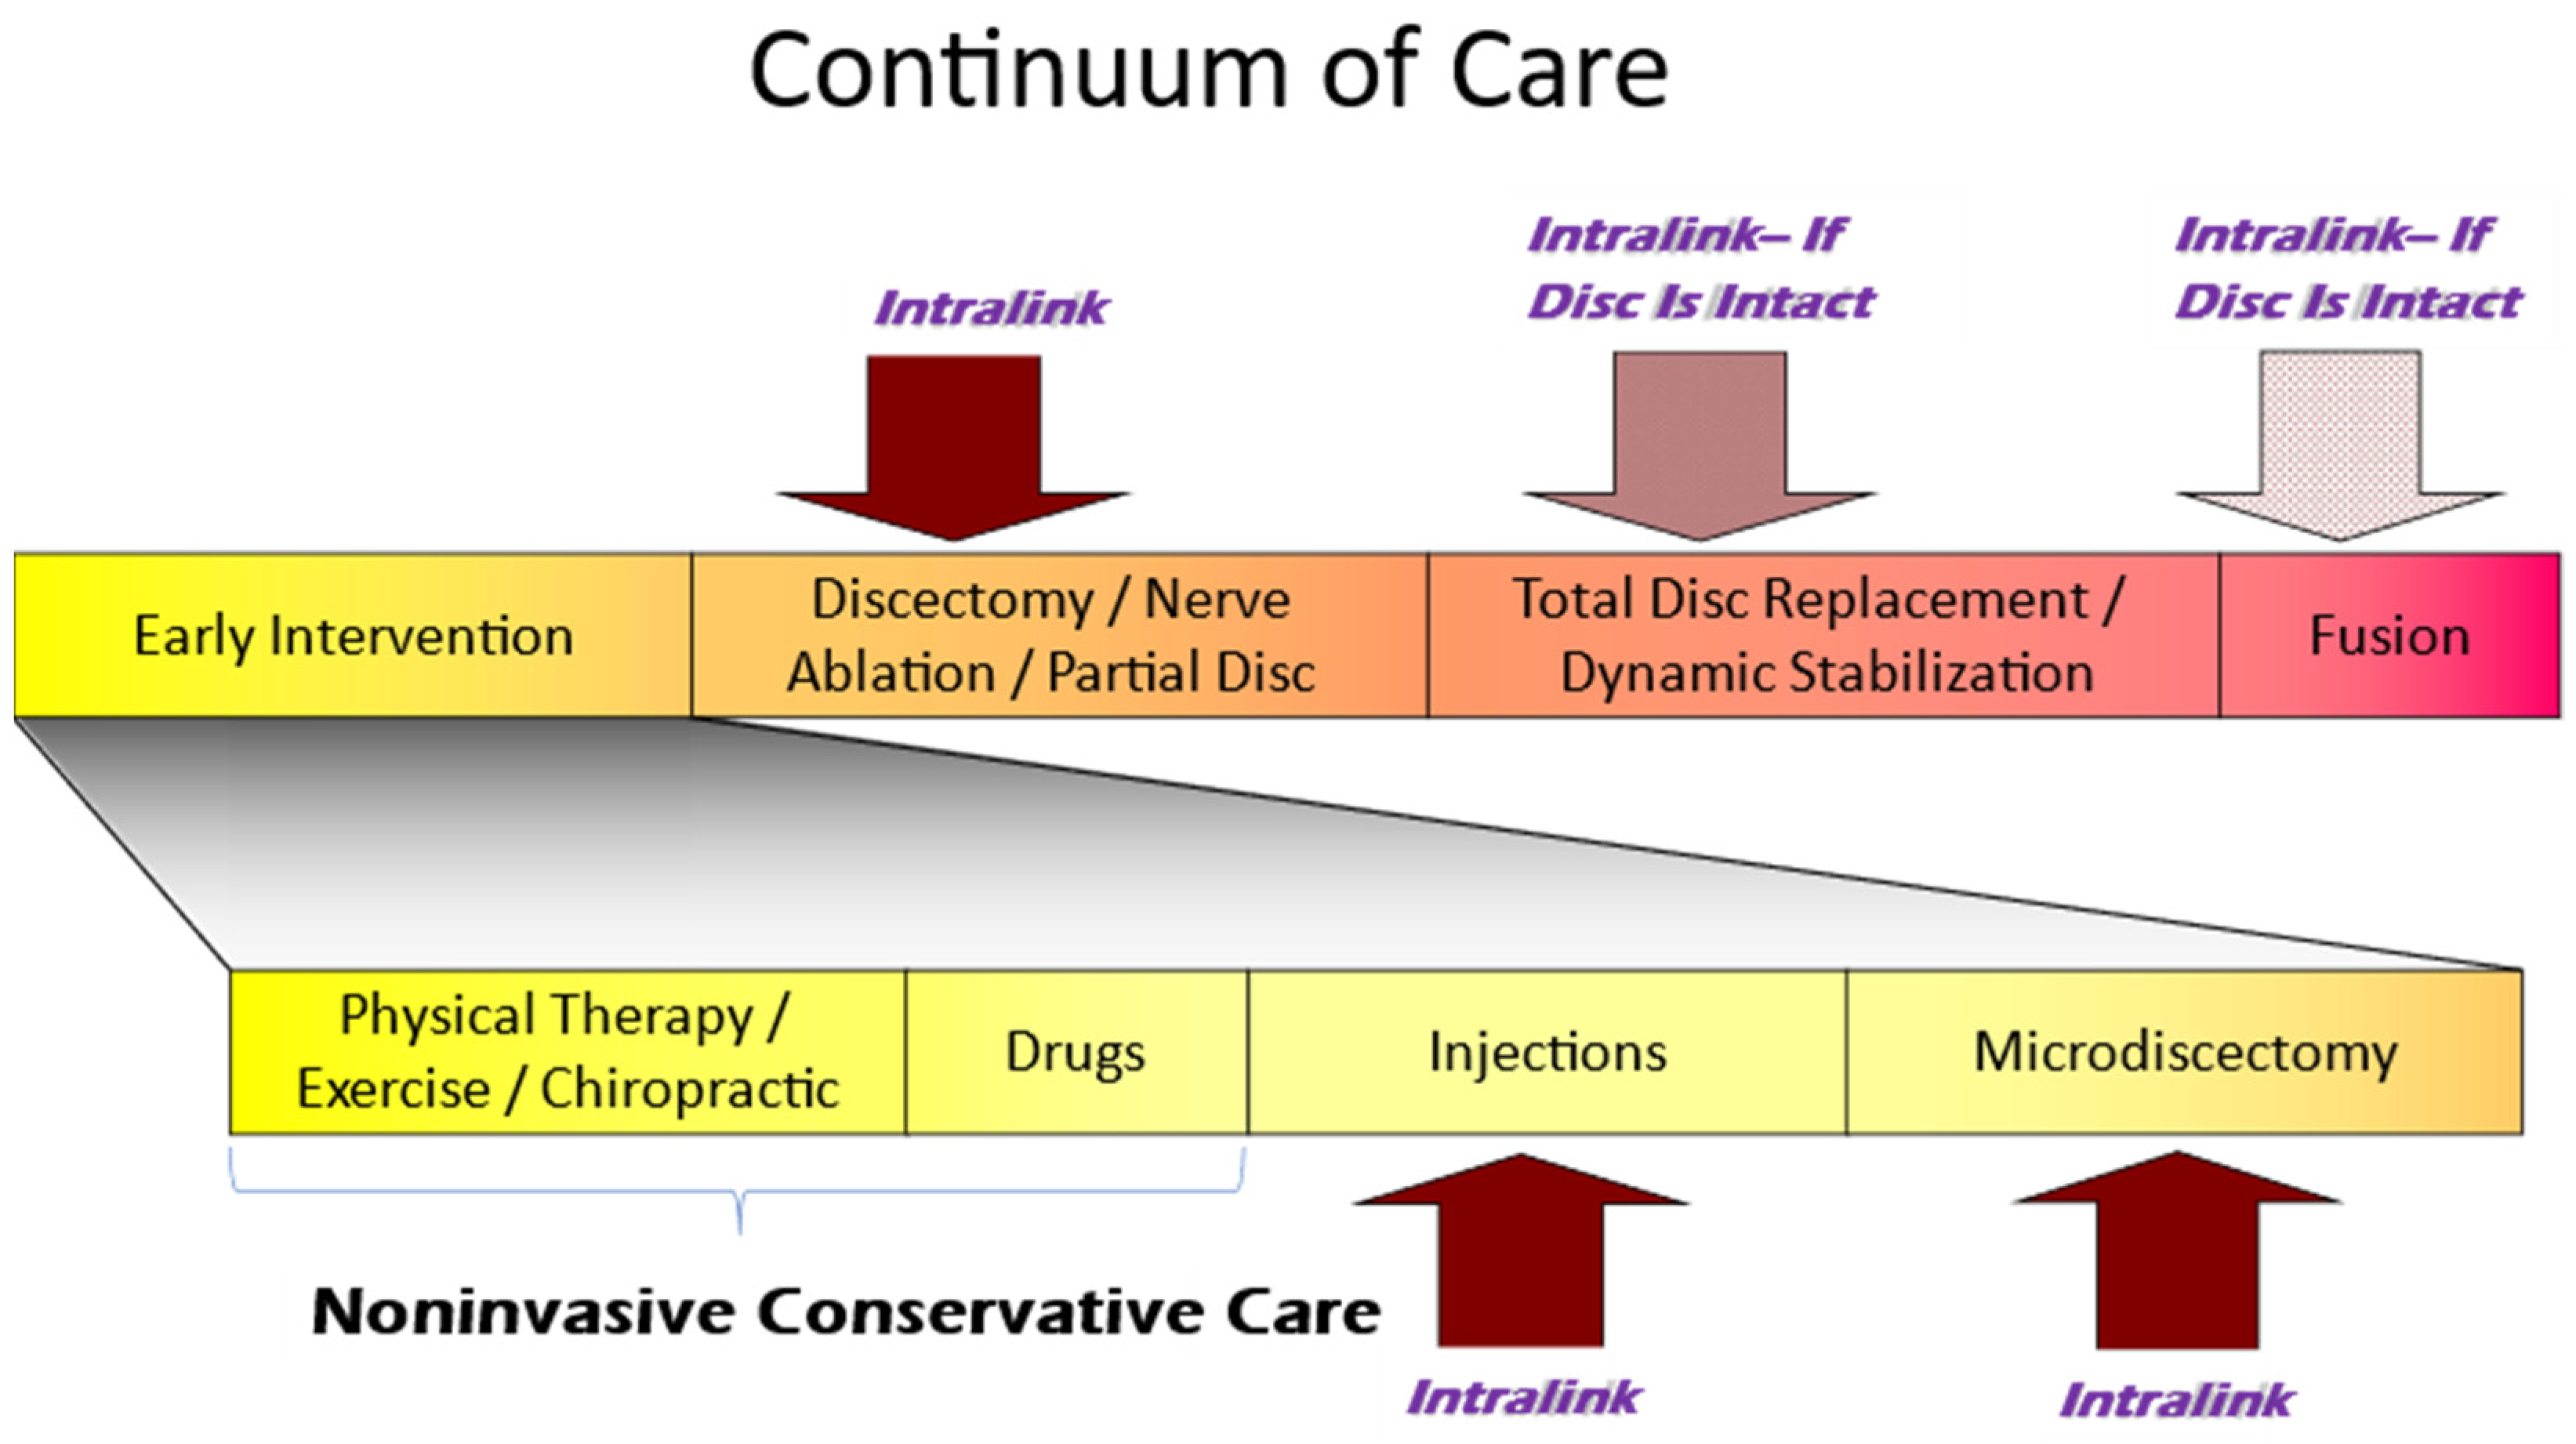

3.5. The Current Continuum of Care for Discogenic LBP